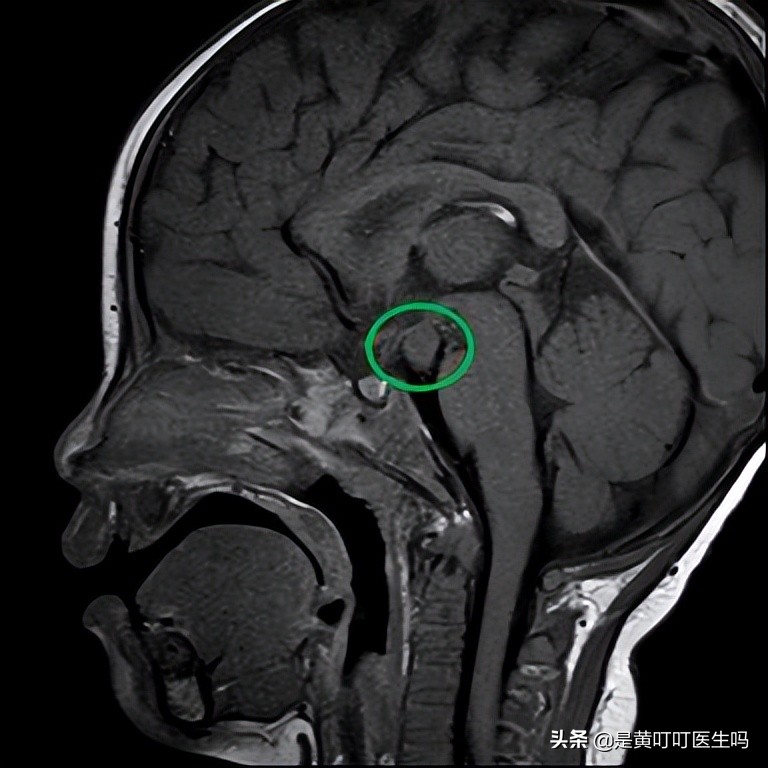

病变在这里

宝宝最后的诊断是“下丘脑错构瘤”,也叫“灰结节错构瘤”。